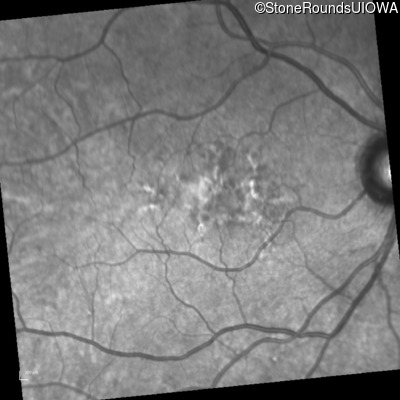

Visit at age: 52 years

Fundus Photography - Right - 20/25 +2

Exemplar

Fundus Photography - Left - 20/50 -1

Fundus Montage - Right - 20/25 +2

Fundus Montage - Left - 20/50 -1